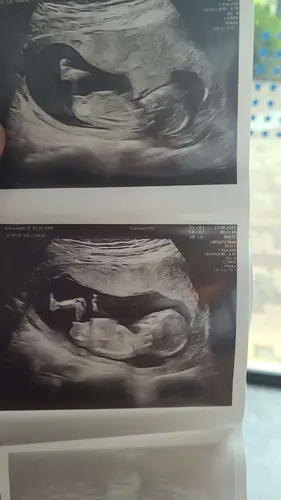

Ik denk een meisje, maar ook dit topic zal gesloten worden net als al je an ...